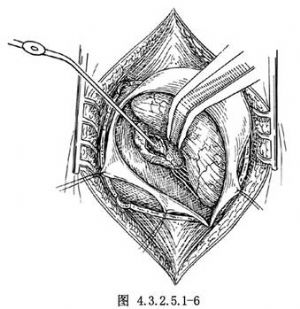

4.切除腫瘤 一般先電凝腫瘤包膜,縱行切開,用吸引器、活檢鉗或刮匙行囊內腫瘤切除(圖4.3.2.5.1-6)。如切除腫瘤時出血較多,可先從腫瘤周邊遊離,進入腫瘤下極。內側與上極的小供血動脈一一電凝後切斷,再繼續從囊內切除腫瘤。囊內切除瘤組織愈多,腫瘤包膜塌陷愈好,有利於腫瘤切除。